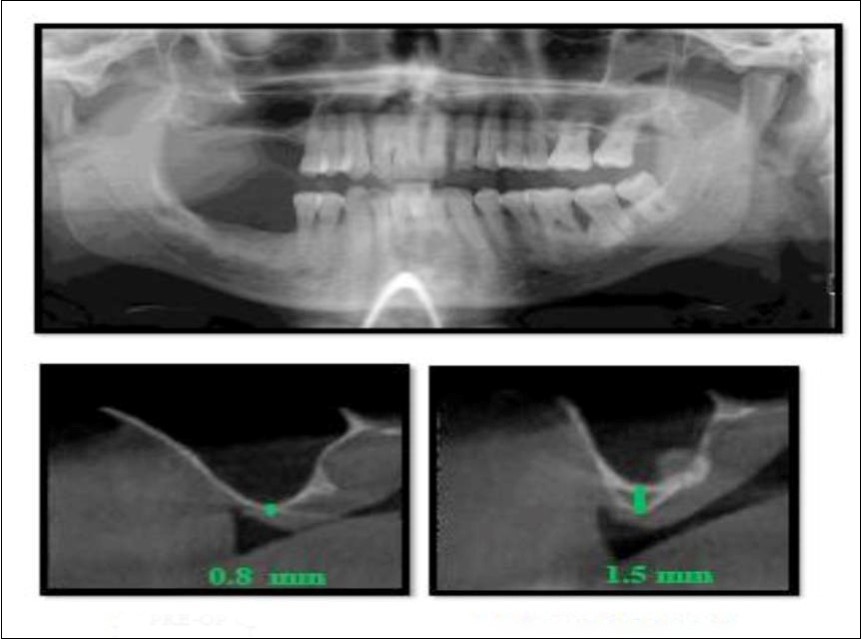

With a pre-operative residual bone height of 0.8 mm in 16 region and 1.5 mm in 17 region, direct sinus augmentation was carried-out in a 40 year old male patient followed by implant placement of 3.75 x 11.5 dimensions as a single step procedure. Lateral window was created and synthetic graft material was dispensed through the lateral osteotomy site to maintain the elevated sinus membrane followed by placement of two dental implants through the crestal approach measuring 3.75 x 11.5 mm under local anesthesia and strict aseptic protocols. At the end of 6 months, a CBCT scan was advised to evaluate the increase in bone height which was 11 mm and 10.8 mm in 16 and 17 region respectively. (Figure 1, Figure 2)

Figure 1.Pre-operative Orthopantomograph and cross sections of CBCT showing residual alveolar bone height

Figure 2.Post-operative Orthopantomograph and cross sections of CBCT showing an increase in residual alveolar bone height